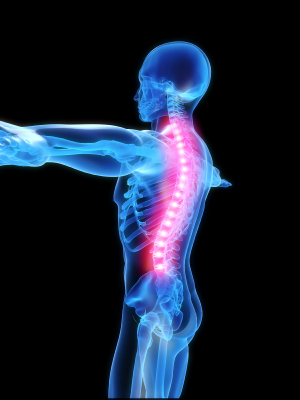

What is the ideal spinal alignment?

Notice that from the front, the spine is straight. From the side, however, the spine has three essential curves: a neck curve, a ribcage curve and a lower back curve.

The normal curves in the spine as seen from the side are extremely important for your health. These curves help absorb shock, allow for proper movement, and evenly distribute the normal forces on the spine.

If a spine deviates from the normal configuration, such as a significant increase, decrease or reversal of any of the curves, the spine is considered to be misaligned.